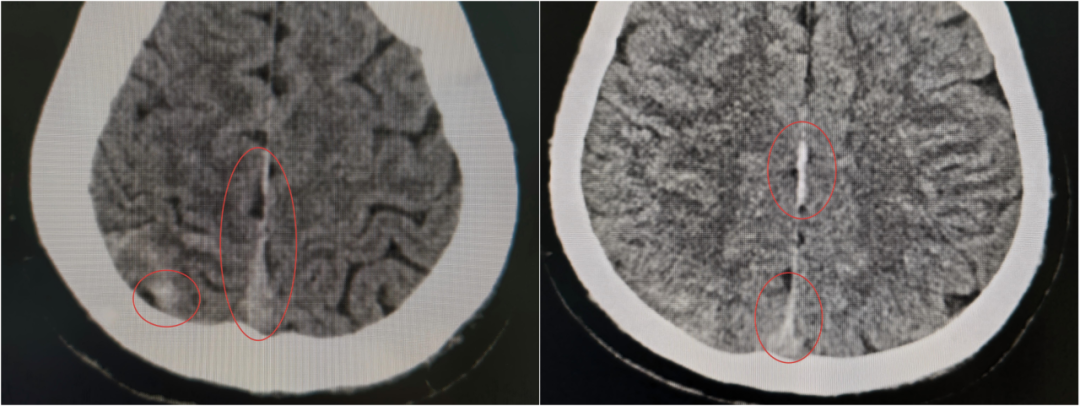

小徐颅脑内部存在多处出血点,枕骨破裂

争分夺秒,必须环环紧扣。完成必要指标监测后,立即将小徐送往放射科,10分钟内完成急诊CT检查。结果显示:枕骨破裂,蛛网膜下腔出血。

当第二次 CT 提示出现硬膜外血肿、蛛网膜下腔出血范围进一步扩大时,虽然符合预判,但每个人都清楚:出血量和点位的不可控,血肿扩大可能压迫脑组织,任何微小变化都可能改写结局,之前的一系列努力可能功亏一篑。

伤情再次变化,出血范围扩大